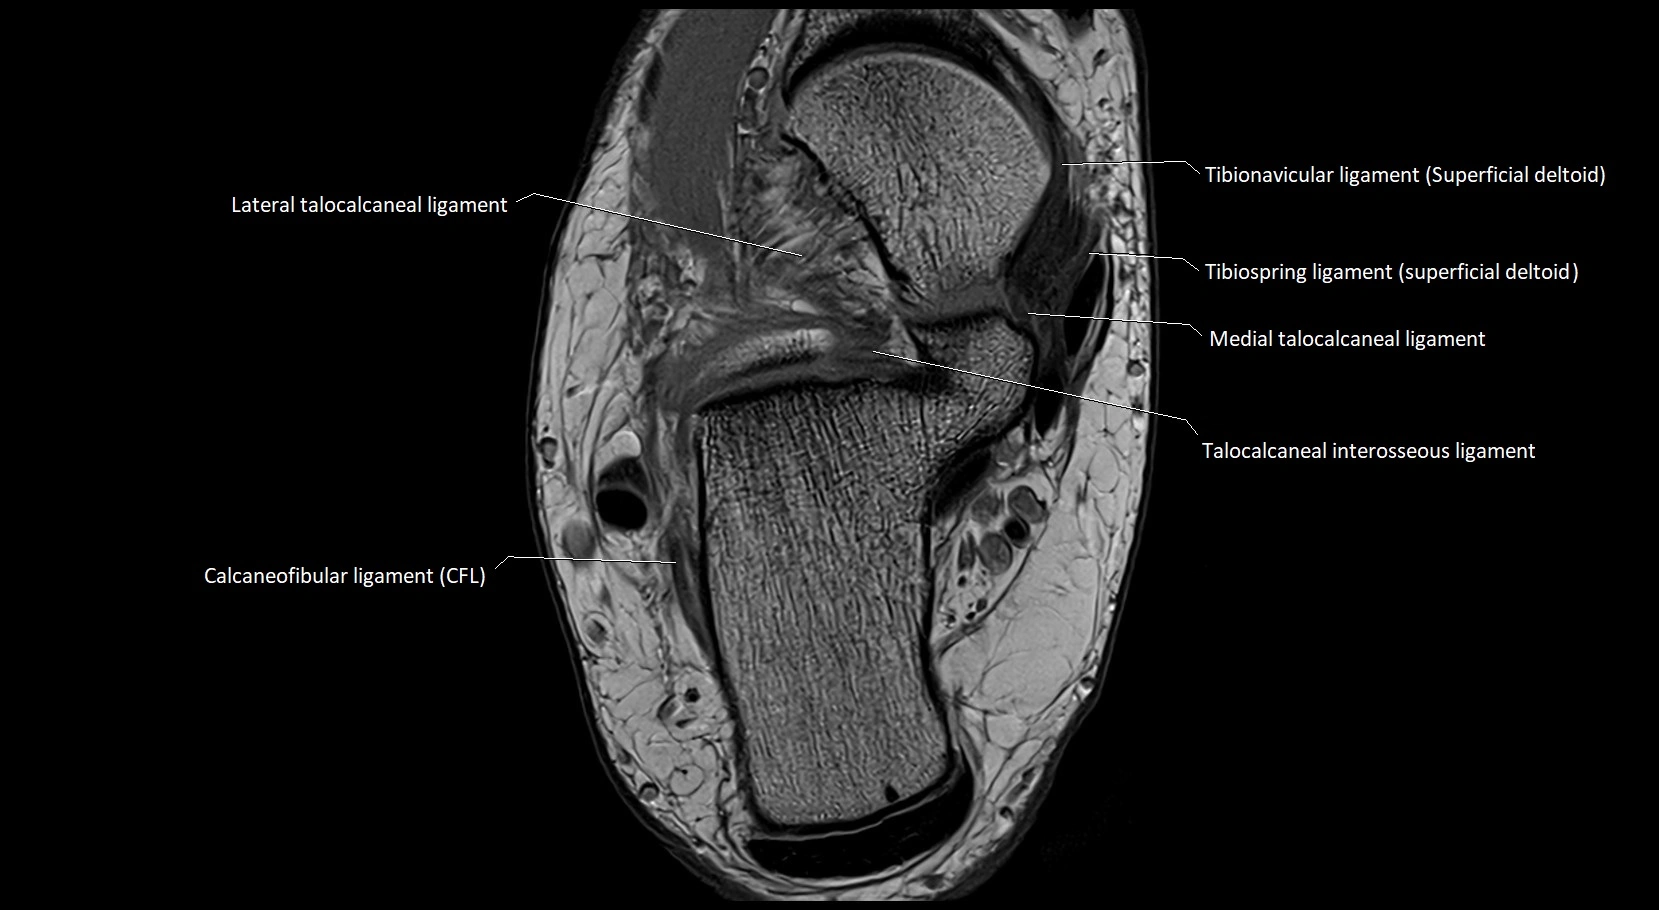

MRI image

image